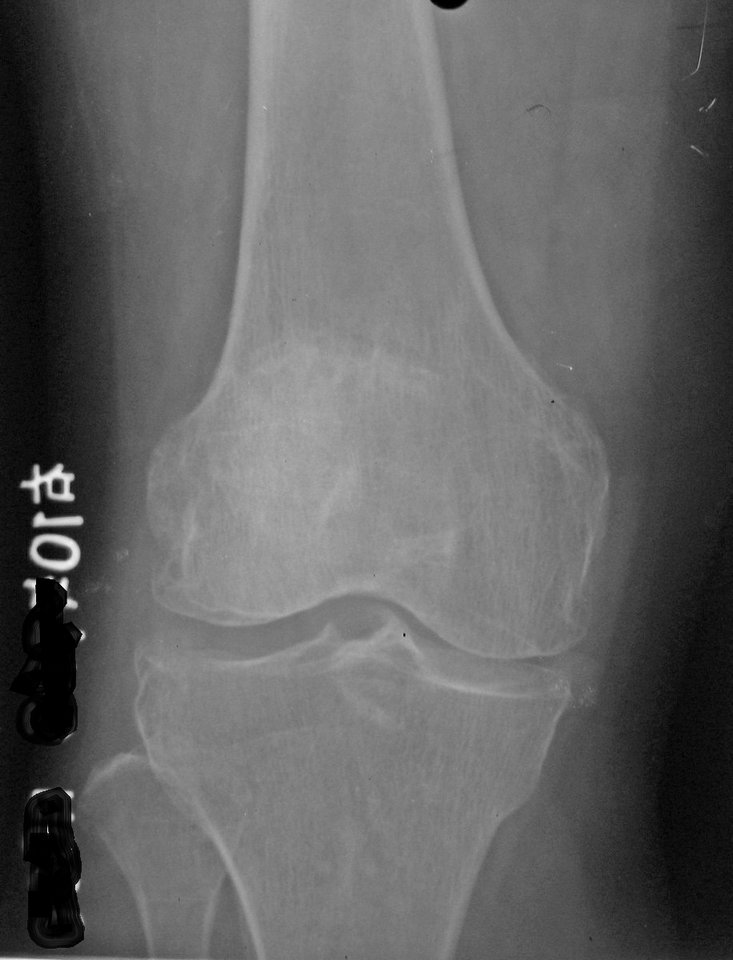

以下是引用拾荒者在2010-7-5 21:08:00的发言:[br]1.膝关节退行性变;2.颈椎未见明显异常。

以下是引用hexue在2010-7-5 22:47:00的发言:[br]1.膝关节退行性变;2.颈椎未见明显异常。 [br] [br]

以下是引用随光逐影在2010-7-6 7:11:00的发言:[br]病例1:双膝关节退行性骨关节病。[br]病例2:1)颈椎未见明确异常。2)一侧下颌智齿横位阻生。